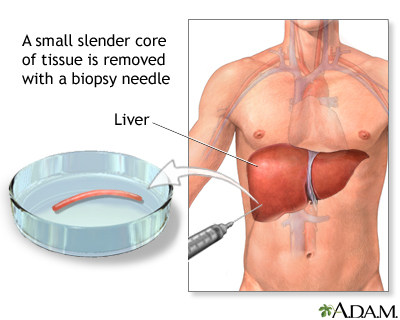

Liver Biopsy

A liver biopsy is not always needed for diagnosis of cirrhosis. It may be performed for confirmation if other tests are inconclusive. A liver biopsy can also help determine the cause of cirrhosis, the extent of damage, and treatment options.

A biopsy involves a doctor inserting a thin biopsy needle, usually guided by ultrasound, to remove a small sample of liver tissue. Local anesthetic is used to numb the area. You may feel pressure and some dull pain. The procedure takes about 20 minutes.

The biopsy may be performed using various approaches, including:

Percutaneous liver biopsy.

Uses a needle inserted through the skin over the liver area to obtain a tissue sample from the liver.

Transjugular liver biopsy.

Uses a catheter (a thin tube) that is inserted in the jugular vein in the neck and threaded through the hepatic vein (which leads to the liver). A needle is passed through the tube, and a suction device collects liver samples.Laparoscopy.

Is a procedure in which the doctor makes a small abdominal incision and inserts a thin tube that contains a tiny camera to view the surface of the liver. The doctor can place small surgical instruments through the tube to take a tissue sample.